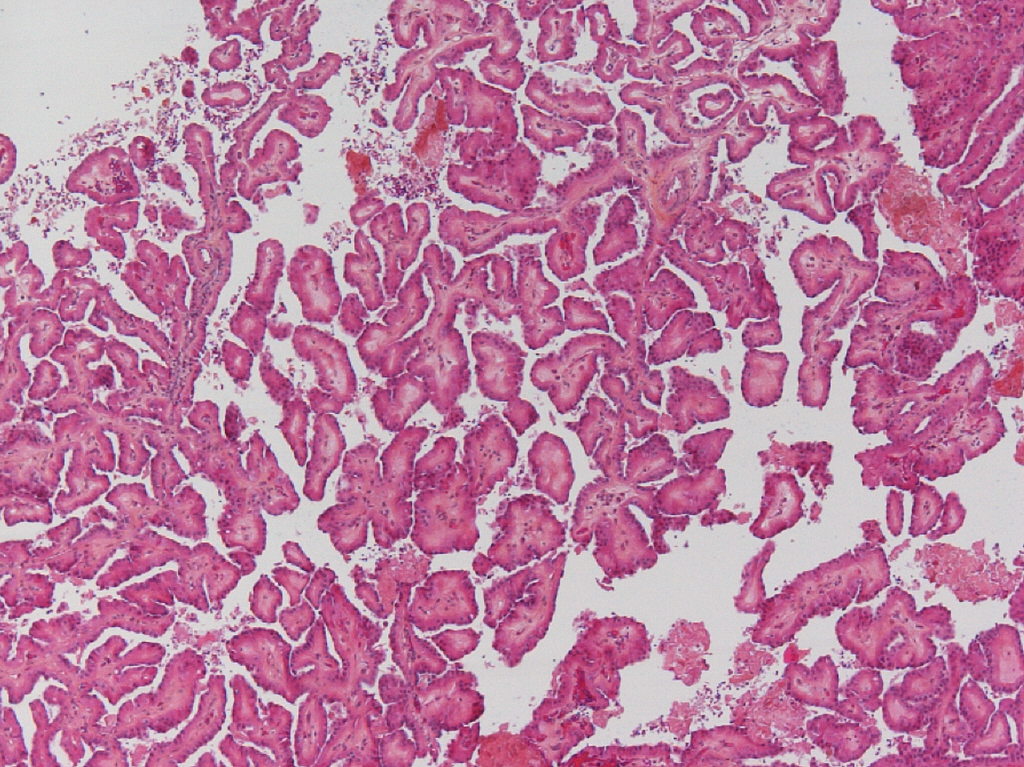

Classification of renal tumors